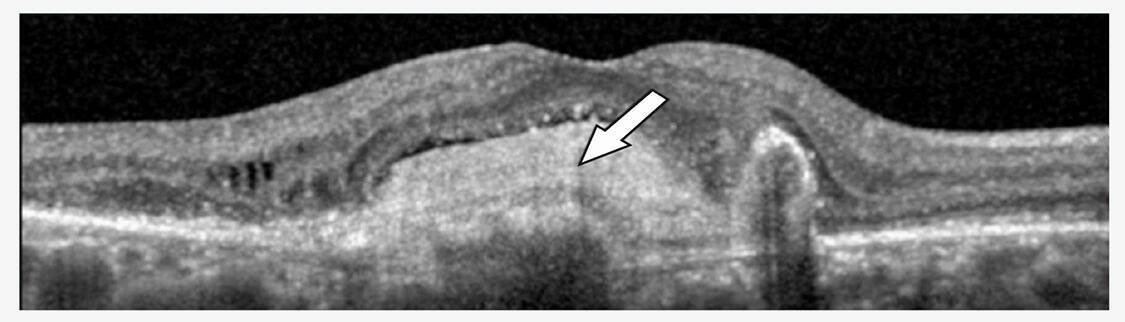

Figure 1. (A) Néovaisseau choroïdien myopique accompagné de fluide sous-rétinien.

(B) OCT B-scan horizontale identifiant du fluide sous-rétinien. Il existe une lésion hyperréflective à bords flous avec une hyporéflectivité postérieure et l’absence d’effraction de l’épithélium pigmentaire. (C) La diffusion tardive à l’angiographie à la fluorescéine confirme le diagnostic.